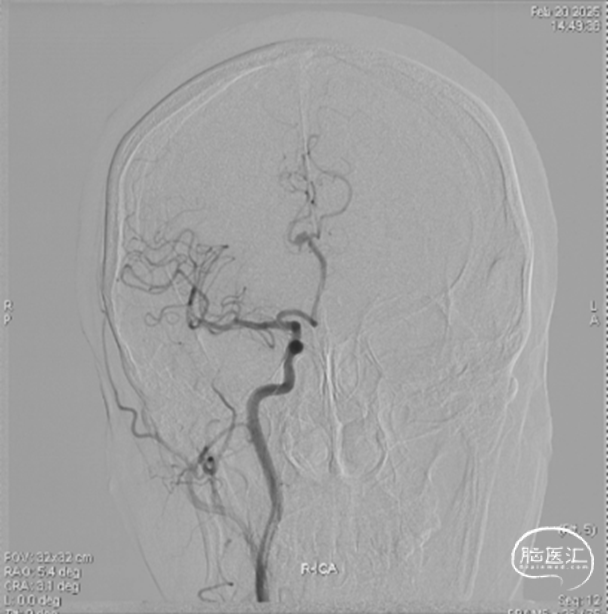

右侧颈内正位造影

载瘤动脉远端血管直径:2.1mm

载瘤动脉近端血管直径:1.8mm

动脉瘤尺寸:瘤颈4.69mm,大小3.25mm*4.21mm*4.24mm;指向右上

近端狭窄:最窄处:0.53mm,远心端2.1mm,近心端2.2mm,长度11.23mm